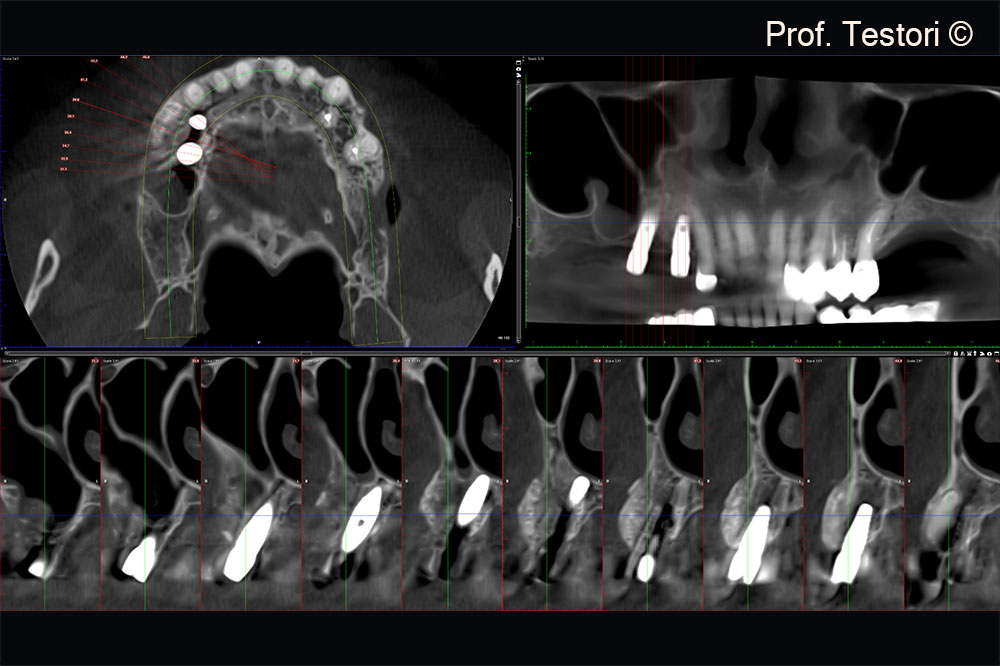

Cone-beam computerized tomography examination after second stage surgery.